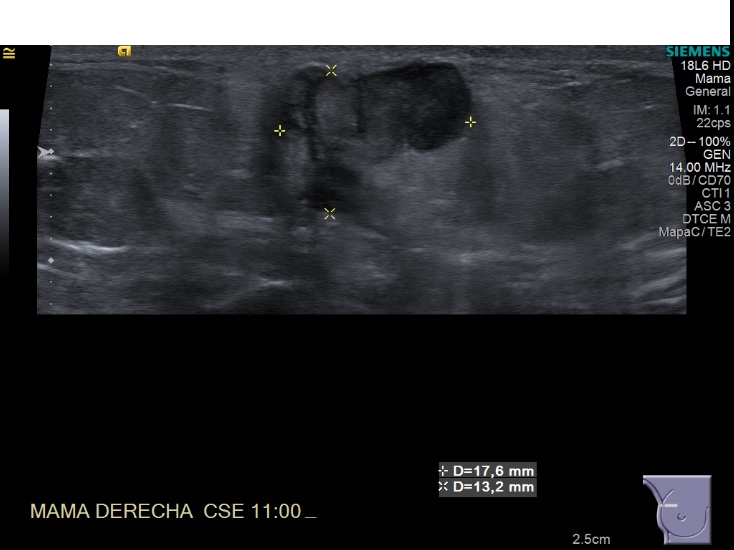

Crioablacion de tumor en mama derecha